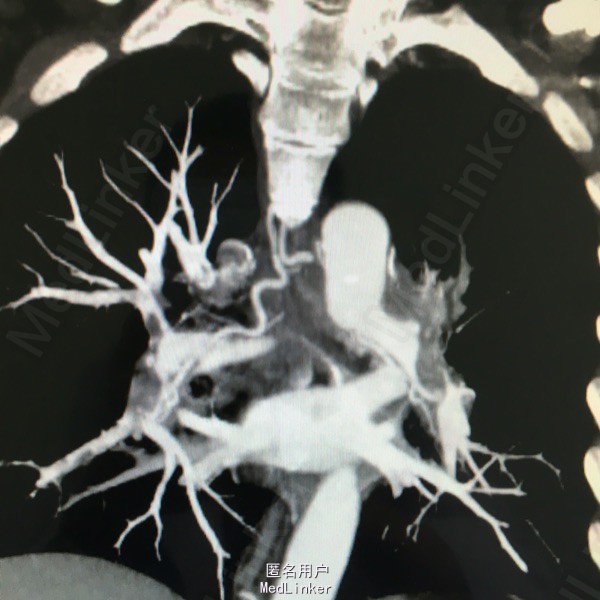

男性,61岁,因气紧3天入院。平时剧烈活动或活动量加大后感气紧。8年前有下肢深静脉血栓,后一直口服阿司匹林。

入院查体见呼吸较平稳,氧饱和度95%左右,嘴唇发紫;CT提示双肺大面积动脉栓塞,心脏彩超提示肺动脉高压,双下肢彩超未见静脉血栓。

慢性肺动脉栓塞,正规抗凝溶栓治疗

对于肺动脉栓塞来讲多数是由于下肢静脉血栓脱落所致,可予以置入腔静脉滤器同时介入下捣栓溶栓。但该患者下肢已无血栓,而且通过症状来看考虑慢性肺动脉栓塞,予以长期正规抗凝治疗十分重要。